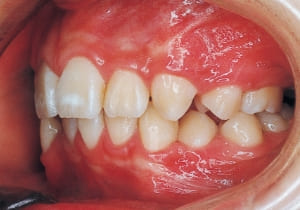

7 At start of Phase 1 Treatment 3-28-’88

8 Phase 1 Treatment progress 1-25-’89 10 months after start of treatment

9 After Phase 1 Treatment 5-24-’89 1 year and 2 months after start of treatment

The first phase of treatment involved extracting the left and right maxillary deciduous canines. The space created was used to forcibly retract the four anterior teeth, thereby aiming to improve lip closure function (6–9, 11). Morphological changes suggest that lip function differed before and after treatment (6, 9). Subsequently, the first premolars erupted, but extraction is planned to secure space for canine eruption (10). A Class II molar relationship remains, but the significant overjet has improved (11).